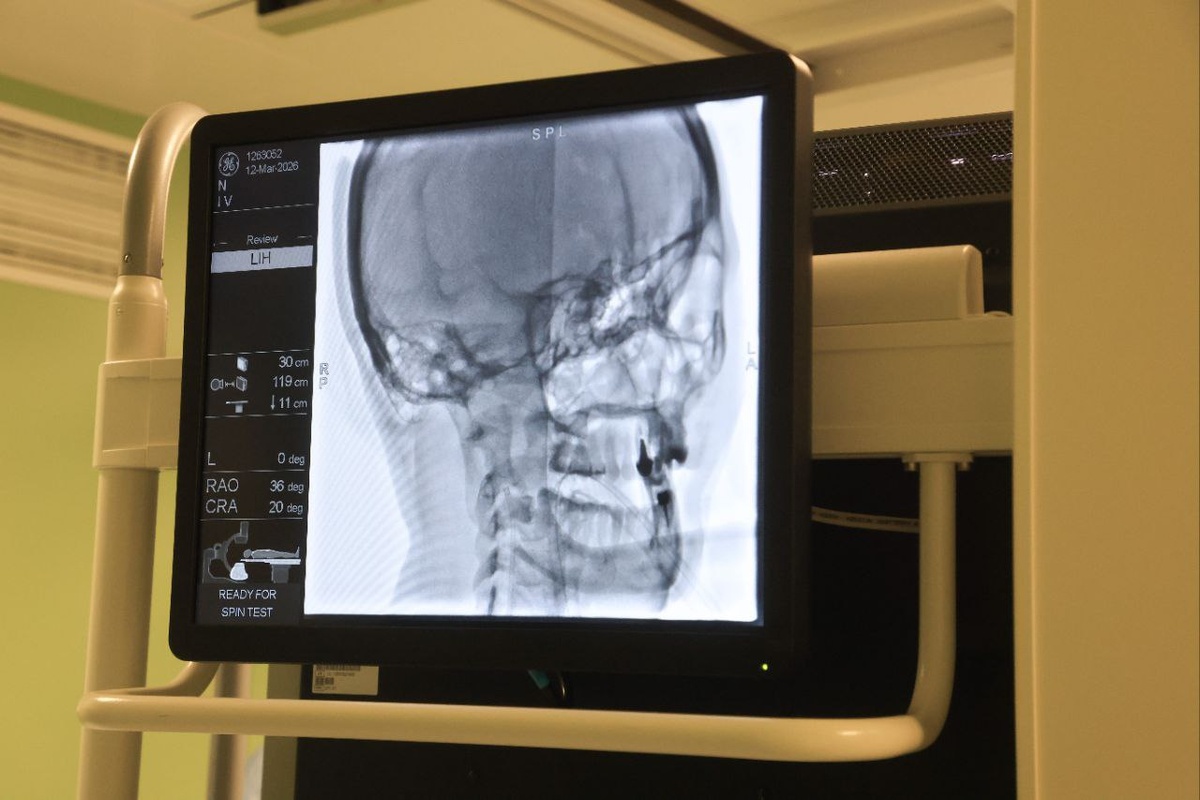

Операция артериовенозной мальформации – жизнеугрожающие сосудистые заболевания головного мозга. #gluzphoto #джанелидзе #нииджанелидзе #операция #головноймозг #операционная

«Джанелидзевские чтения — 2026»: диалог профессионалов в новом формате. Операция артериовенозной мальформации –

жизнеугрожающие сосудистые заболевания головного мозга. #gluzphoto #джанелидзе #нииджанелидзе #операция #головноймозг #операционная